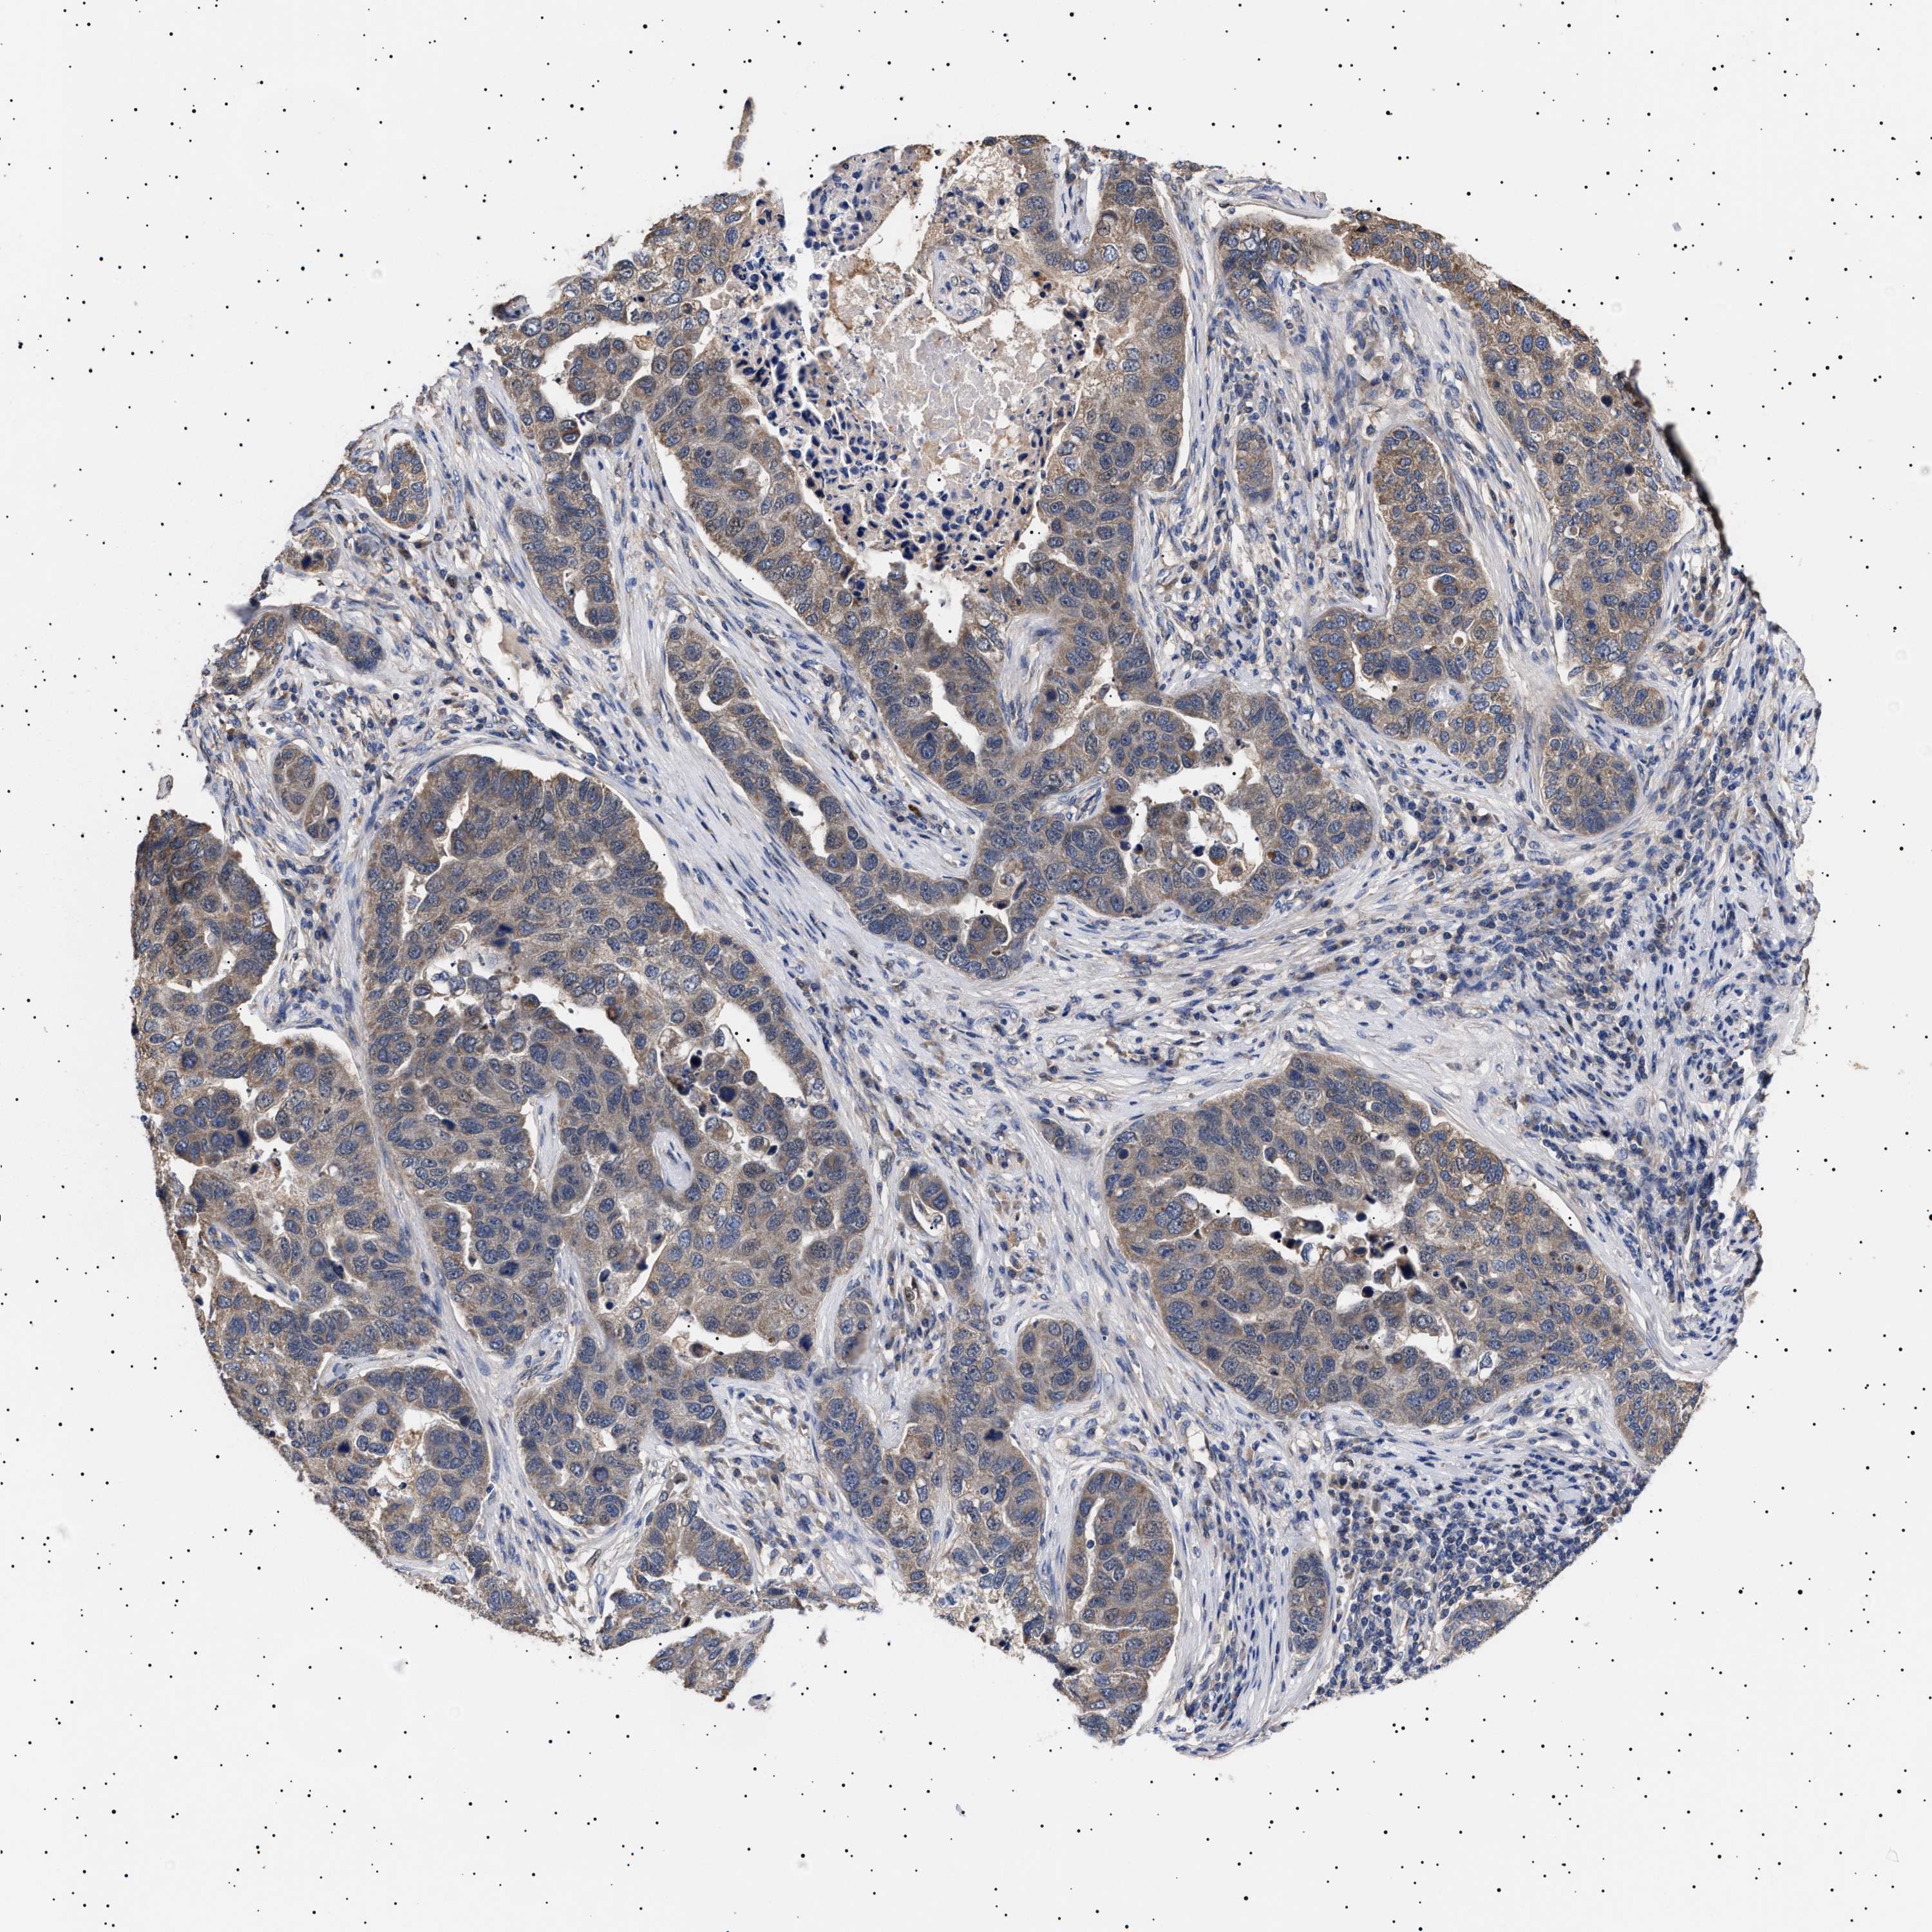

PANCREATIC CANCER - Protein expressioni

A mouse-over function shows sample information and annotation data. Click on an image to view it in a full screen mode. Samples can be filtered based on level of antibody staining by selecting one or several of the following categories: high, medium, low and not detected. The assay and annotation is described here.

Note that samples used for immunohistochemistry by the Human Protein Atlas do not correspond to samples in the TCGA dataset.

Antibody stainingi

Antibody staining in the annotated cell types in the current human tissue is reported as not detected, low, medium, or high, based on conventional immunohistochemistry profiling in selected tissues. This score is based on the combination of the staining intensity and fraction of stained cells.

Each image is clickable and will lead to virtual microscopy that enables deeper exploration of all samples and also displays staining intensity scores, fraction scores and subcellular localization as well as patient and tissue information for each sample.

Antibody HPA021237

Antibody HPA050448

Staining

High

Medium

Low

Not detected

Intensity

Strong

Moderate

Weak

Negative

Quantity

>75%

75%-25%

<25%

None

Location

Nuclear

Cytoplasmic/membranous

Cytoplasmic/membranous,nuclear

Adenocarcinoma, NOS